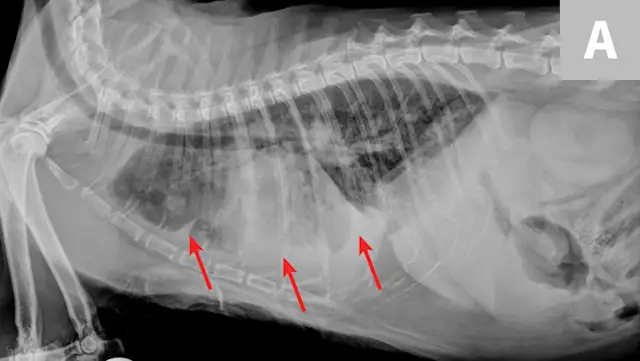

Radiographic evaluation is variable. Classic cranioventral distribution is less common in cats (Figure 3). A bronchial pattern is most common; however, bronchointerstitial, alveolar, and more structured pseudonodular patterns can occur.6,8 Occasionally, pulmonary abscesses may be appreciated and resemble pulmonary neoplasia (Figure 4).

FIGURE 4

Radiograph of pulmonary abscessation. The pulmonary nodules (arrows) could be mistaken for pulmonary neoplasia. The margins of these nodules are slightly less well demarcated than in neoplasia. Improvement was achieved with antibiotic therapy.